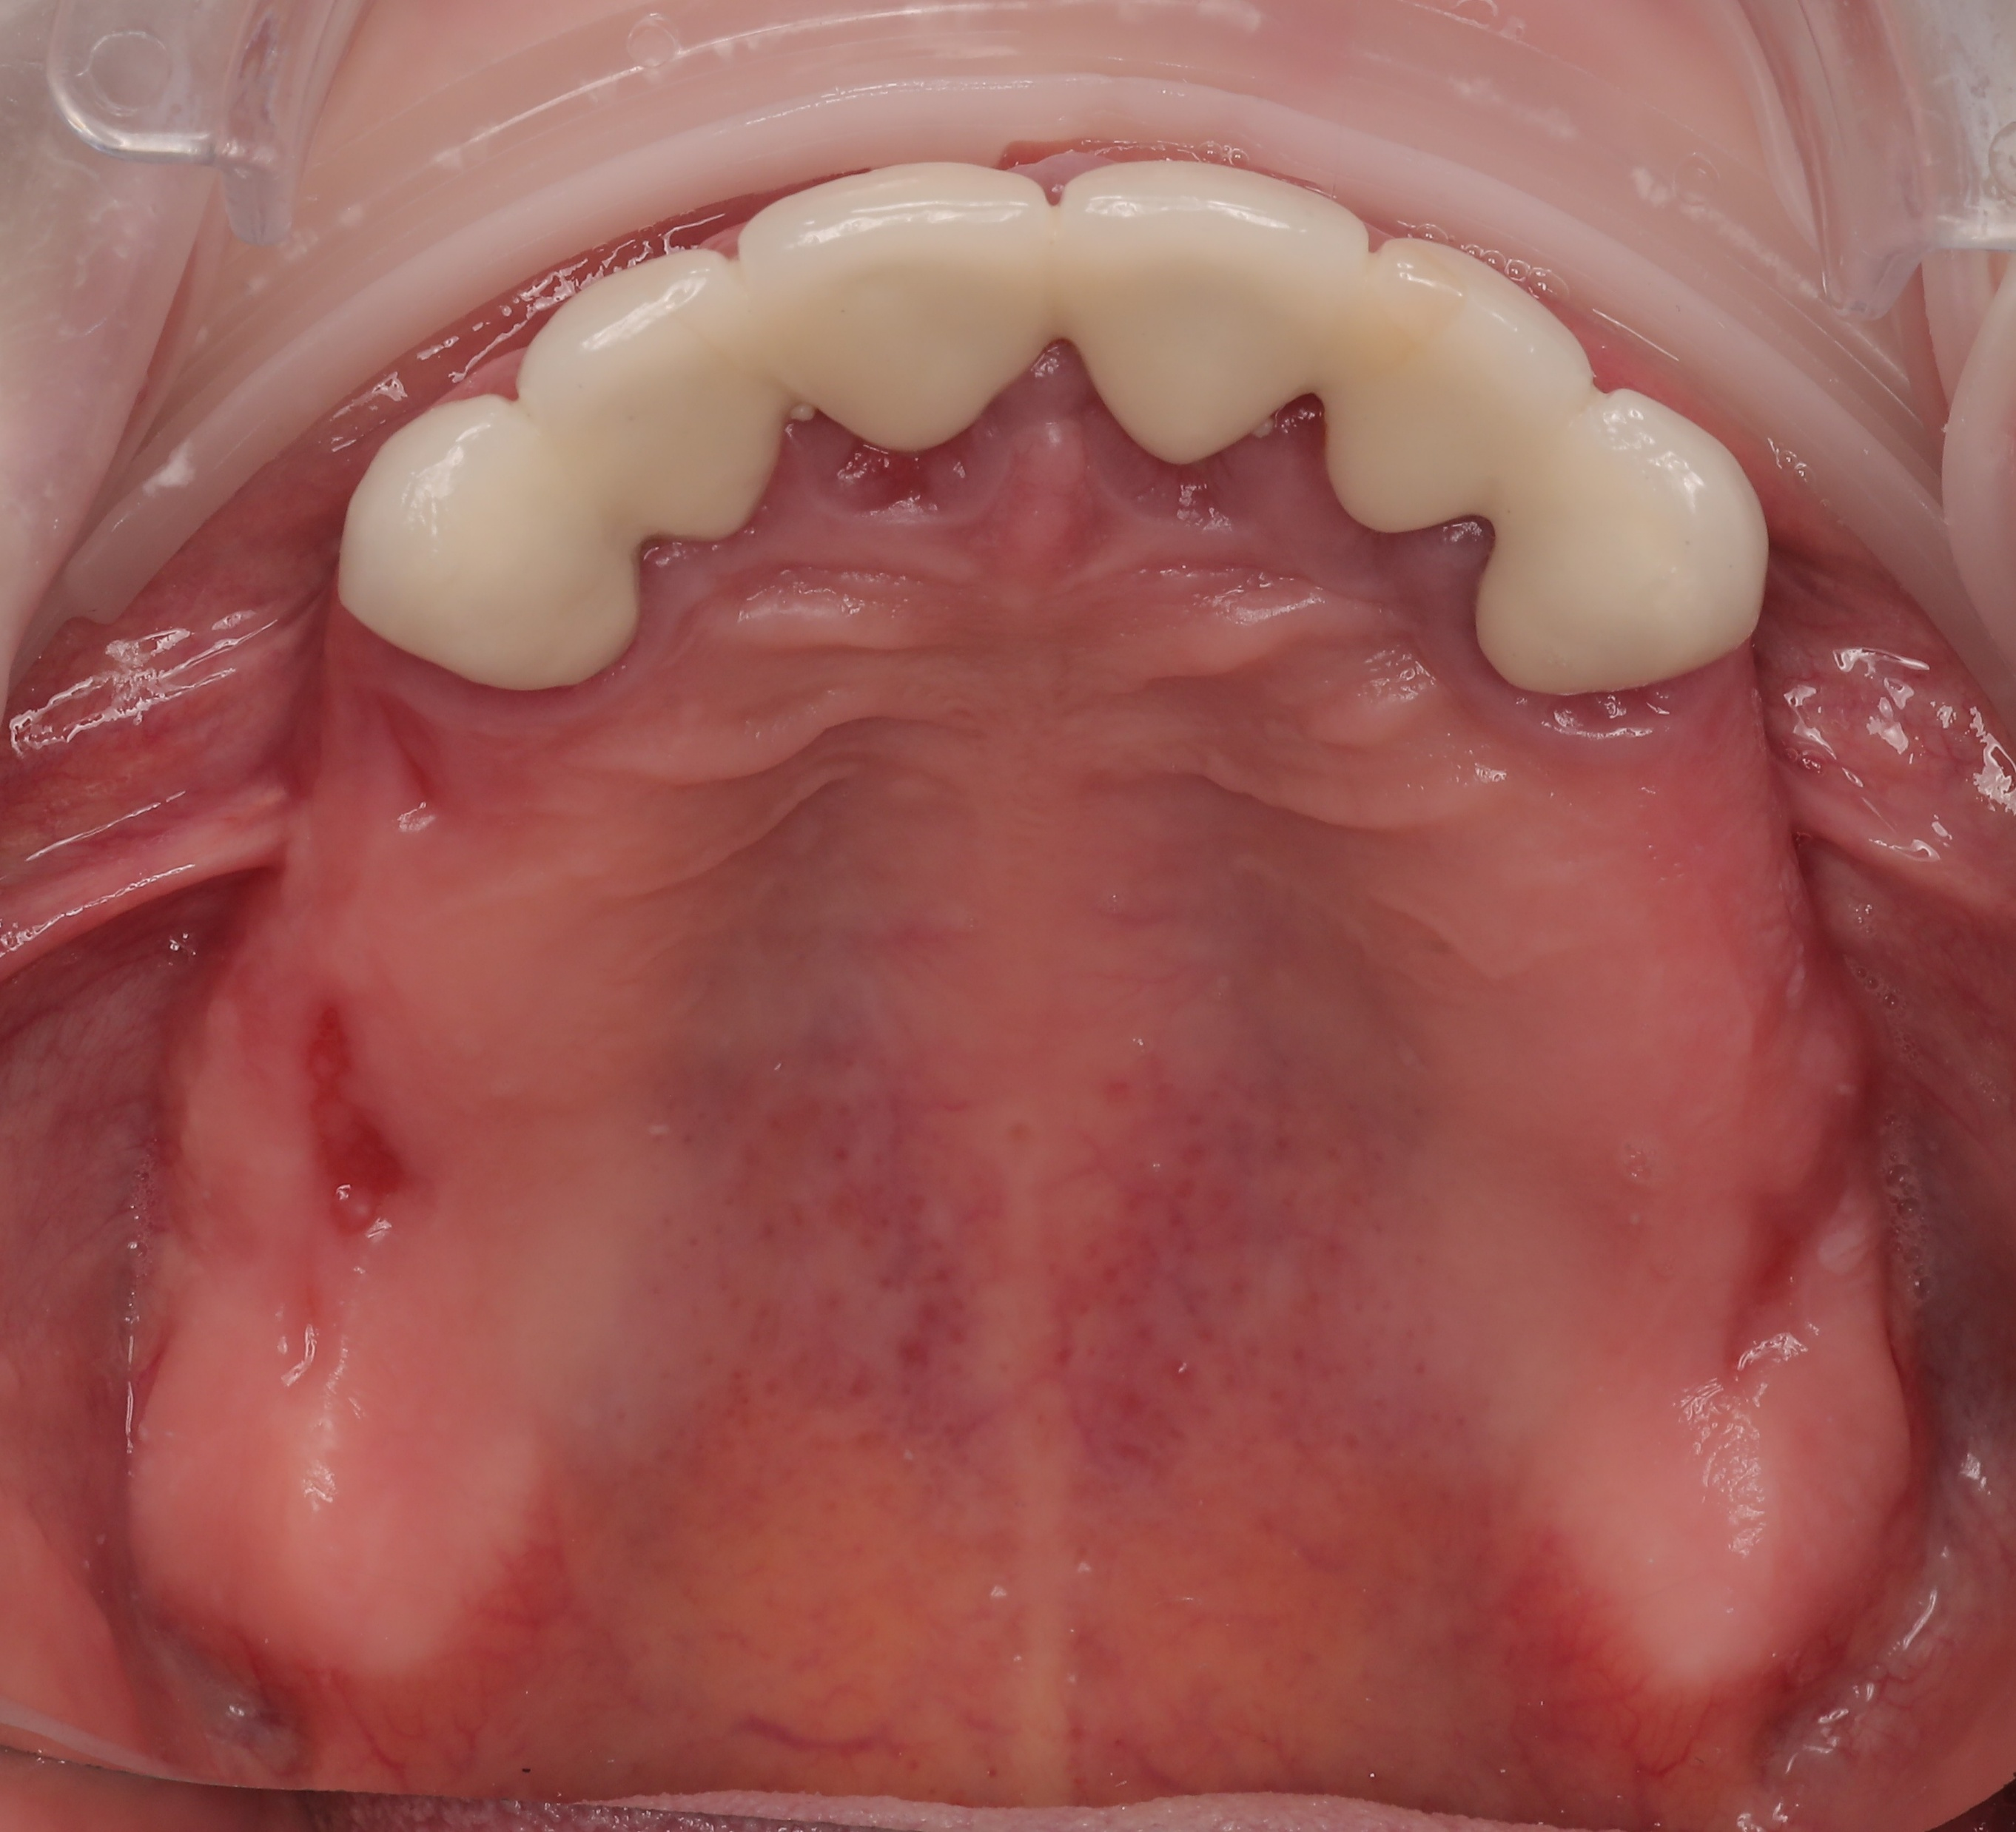

Based on the high-fidelity digital impressions, same-day resin provisional prostheses were fabricated and delivered immediately after surgery. The precision of the IPG scan ensured a successful same-day provisional bridge delivery and secure retention using Rosen screws without the need for titanium bases. Post-operative Orthopantomogram (OPTG) confirmed accurate seating and stable connections across all implants, with a 2 mm occlusal clearance maintained in the molar region to ensure functional safety during the initial healing phase.